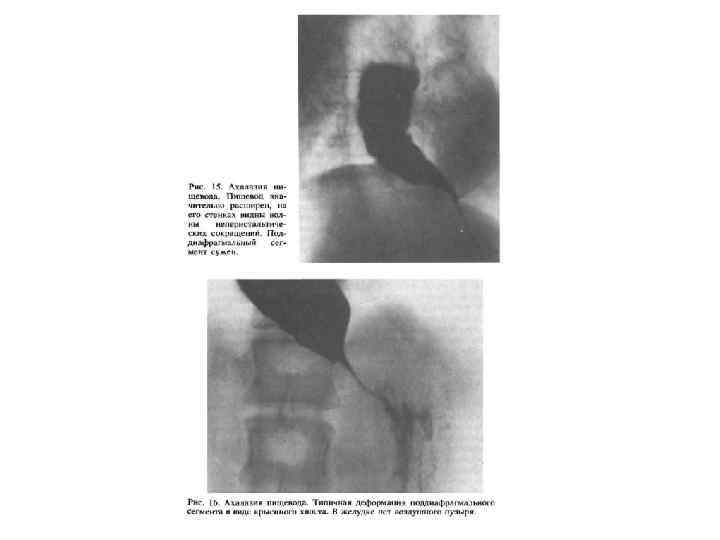

Классификация ахалазии • I тип характеризуется умеренным сужением дистального отрезка пищевода и незначительным супрастенотическим расширением пищевода (до 6 см). Сохраняется его цилиндрическая или овальная форма. • При ахалазии II типа отмечается выраженное сужение дистальной части пищевода и его значительное супрастенотическое расширение (иногда до 16 18 см), из за чего пищевод часто принимает N образную форму. В зависимости от вида дискинезии грудного отдела пищевода выделяют гипермоторную и гипомоторную формы ахалазии кардии, а в зависимости от тяжести клинического течения заболевания стадии компенсации и декомпенсации.

Стадии (рентгенологически) I – коническое сужение, барий быстро попадает в желудок II – расширение в грудной части пищевода, в которой скапливается жидкость III – резкое расширение пищевода. Опорожнение пищевода задерживается на несколько суток

Ахалазия пищевода II III стадии